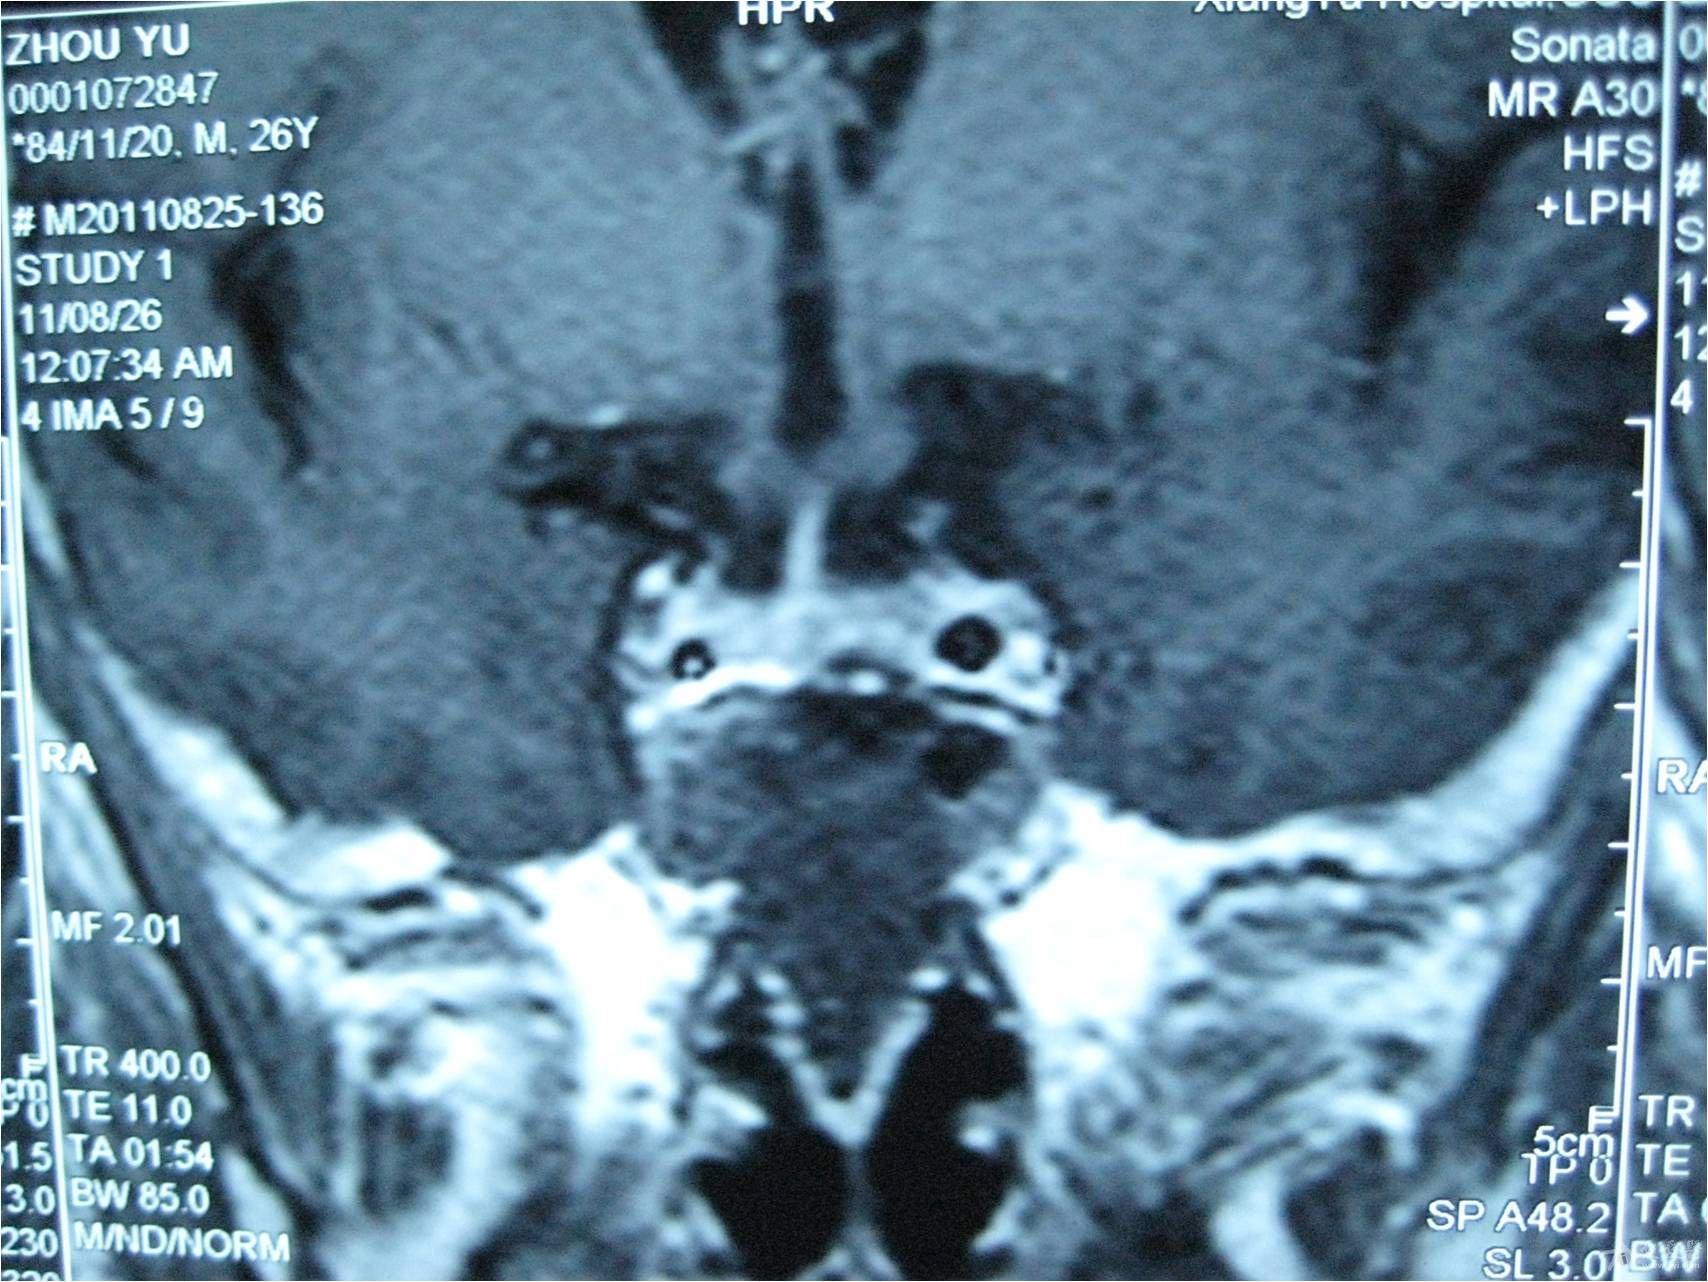

脑垂体的核磁共振检查结果请分析

(红色圈内为垂体瘤)术前ct(红色圈内为垂体瘤)术前mri为进一步治疗,吕

了解了他的病史,得知他在四年前体检时,头部磁共振提示"垂体良性肿瘤"

并有所加重,视力也急剧下降,还出现呕吐,外院颅脑ct提示垂体瘤,患者即